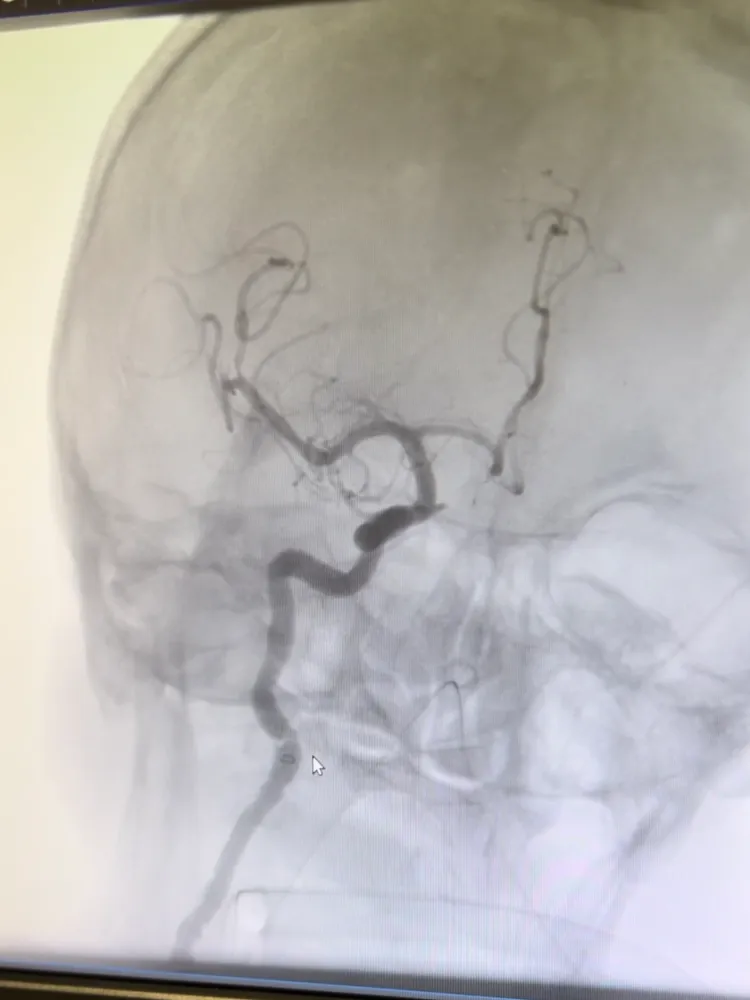

Girişimsel Nöroloji Uzmanı Doç. Dr. Ezgi Sezer Eryıldız tarafından uygulanan trombektomi işlemi ile hastanın felç bulguları dakikalar içinde geriledi. İnme şüphesiyle hastaneye getirilen Yusuf Sezer, bilinci bulanık, konuşma güçlüğü yaşayan ve vücudunun sağ tarafında güç kaybı bulunan bir şekilde acil servise ulaştı. Yapılan görüntüleme yöntemlerinde şah damarının tıkalı olduğu tespit edildi. Hızla anjiyo ünitesine alınan hasta, Girişimsel Nörolog Doç. Dr. Ezgi Sezer Eryıldız’ın gerçekleştirdiği başarılı trombektomi operasyonu ile sağlığına kavuştu. Doç. Dr. Ezgi Sezer Eryıldız: “Dakikalar İçinde Belirtiler Geriledi” Tedavi süreci hakkında bilgi veren Doç. Dr. Eryıldız, erken müdahalenin inme hastalarında hayat kurtarıcı olduğuna dikkat çekerek şu açıklamalarda bulundu: “Hastamız Yusuf Sezer bize inme belirtileri başladıktan kısa süre sonra ulaştı. Şah damarının tıkalı olduğunu tespit ettik ve hemen anjiyoya alarak pıhtıyı temizledik. Dakikalar içinde felç bulguları geriledi. Ardından beyin damar tıkanıklığına neden olan durumu araştırarak gerekli tedaviyi düzenledik. Şu an hastamız sekelsiz, yani kalıcı bir hasar olmadan hayatına bağımsız şekilde devam edebiliyor.” Doç. Dr. Eryıldız, inmede geçen her saniyenin önemine dikkat çekerek vatandaşlara şu uyarıda bulundu: “Konuşma bozukluğu, ağızda kayma, kol ya da bacakta ani güçsüzlük gibi belirtiler görüldüğünde vakit kaybetmeden 112 acil servisi aramak gerekiyor. Ne kadar erken müdahale edersek, o kadar çok beyin hücresini kurtarabiliriz. Bu da felç kalma riskini büyük ölçüde azaltır.” Hasta Yusuf Sezer: “Adeta Yeniden Doğmuş Gibi Hissediyorum” Tedavi sonrası duygularını paylaşan Yusuf Sezer ise yaşadığı anları şu sözlerle anlattı: “Yatağa uzanmıştım, bir anda ter bastı. Eşim buz koydu, ama sağ kolumu ve ayağımı hiç hissetmiyordum. Felç olduğumu o an anladım. Ambulansla hemen Manisa Şehir Hastanesi’ne getirildim. Çok iyi bir doktorla karşılaştım, zamanında müdahale ettiler. Şimdi çok iyiyim. Ne elimde ne ayağımda hiçbir sorun kalmadı. Hepsine minnettarım.” Dedi.